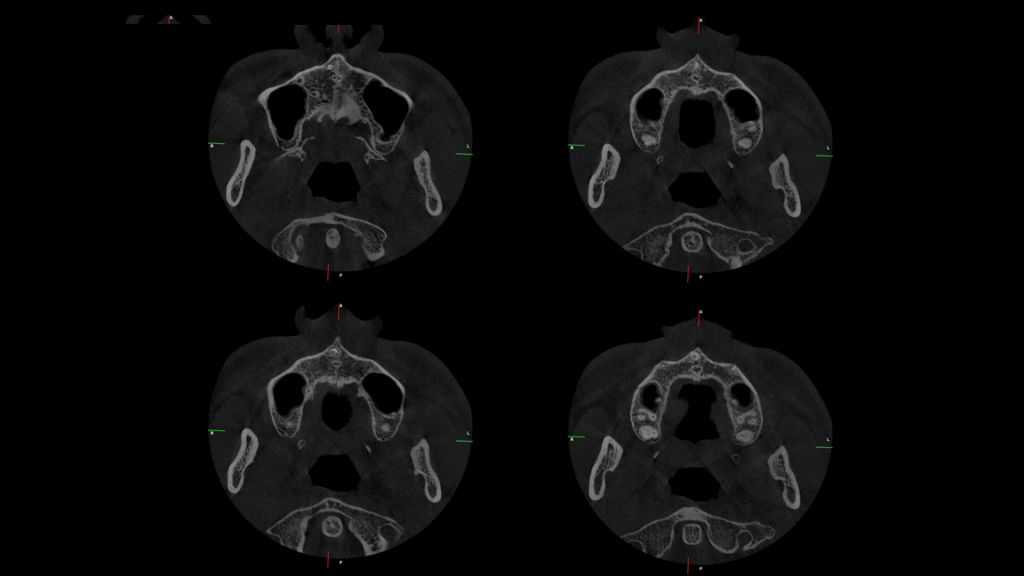

A la evaluación de la tomografía volumétrica (CBCT) en los cortes axiales (Figura 2) y transaxiales (Figura 3), se aprecia pieza supernumeraria en posición invertida localizada en zona anterior del maxilar superior, así mismo se observa disminución de la densidad a nivel coronario y reabsorción radicular externa a nivel del tercio cervical (ameloclasia).

CORTES AXIALES

caso 328 idm cortes axiales